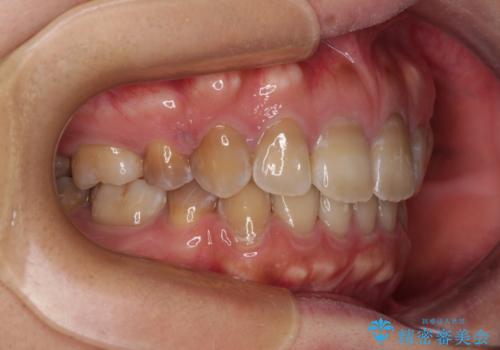

- 口元の突出感を気にして来院された患者様です。

上下前歯が著しく前突している状態であったので、上下左右の第1小臼歯4本を抜歯し、ワイヤー装置にて矯正治療を行うこととしました。

舌の突出癖により、前突になったと考えられたため、舌のトレーニングをしっかりと行うよう指導しました。